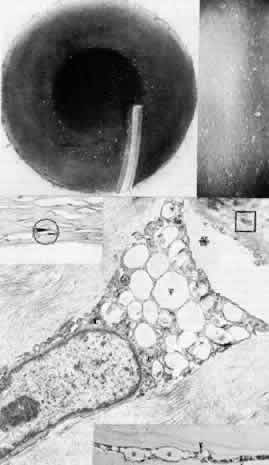

Sclerocornea

In sclerocornea (Fig. 4), the limbus is ill-defined since opaque scleral tissue with fine vascular conjunctival arcades extends into the peripheral cornea. A broad range of corneal involvement is possible, with the most extreme being complete sclerification of the cornea. Ninety percent of cases are bilateral, although generally asymmetric. Most cases are sporadic; there is no known heredity. Sclerocornea is nonprogressive and must be differentiated from interstitial inflammatory conditions and arcus juvenilis (congenital peripheral lipid deposition, also known as anterior embryotoxon). Sclerocornea is associated with cornea plana in approximately 80% of cases.44 Other associated ocular abnormalities include microphthalmos, iridocorneal synechiae, persistent pupillary membrane, dysgenesis of angle and iris, congenital glaucoma, colobomas, and posterior embryotoxon of the fellow eye.45 Somatic abnormalities sometimes occur along with associated chromosomal abnormalities; they include mental retardation, deafness, and craniofacial, digital and skin abnormalities.44

Fig. 4. Sclerocornea. Schematic drawing of ocular features Top left. In a minimally affected patient with additional findings of ptosis, strabismus, and hearing loss, only the peripheral cornea is opacified. Top center. In this advanced case with chromosomal translocation and multiple congenital abnormalities, the entire cornea is sclerified and the fine vascular arcades extend centrally from the conjunctiva and sclera. Top right. Light micrograph of anterior cornea shows edematous disorganization of epithelium, fragmentation of Bowman's membrane (B), and interstitial vascularization (V) (hematoxylin-eosin, × 200). Middle left. Transmission electron micrograph of normal human corneal stroma is shown for comparative purposes. Note uniform 240- to 260-nm collagen fibril diameter (× 50,000). Middle right. Transmission electron micrograph of sclerocornea at same magnification shows disorganized array of collagen fibrils that measure as much as three times normal diameter (× 50,000). Bottom. Transmission electron micrograph of posterior cornea shows abnormal Descemet's membrane of less than 1μm thickness (DM, bracketed) and attenuated endothelial cells (× 10,500). (Schematic. Grayson M: Diseases of the Cornea, p 32. St. Louis, CV Mosby, 1979; Top center and right. Rodrigues MM, Calhoun J, Weinreb S: Sclerocornea with an unbalanced translocation [17p, 10q]. Am J Ophthalmol 78:49, 1974)

Ultrastructural studies22,46,47 have shown the involved stroma to assume the morphologic features of scleral tissue, with irregularly arranged collagen fibrils of variable and immensely enlarged diameter for corneal tissue (up to 150 nm, comparable to normal scleral collagen). The precise lamellar organization of normal corneal stroma is not present; thus optical clarity is not achieved. Various abnormalities of endothelium and Descemet's membrane exist, from attenuation to focal absence. Descemet's membrane is generally thin, with multilaminar deposition of basement membrane-like collagen.

Pathophysiologically, sclerocornea may result from developmental arrest of limbal differentiation during neural crest migration, as occurs with the other mesenchymal dysgeneses.22